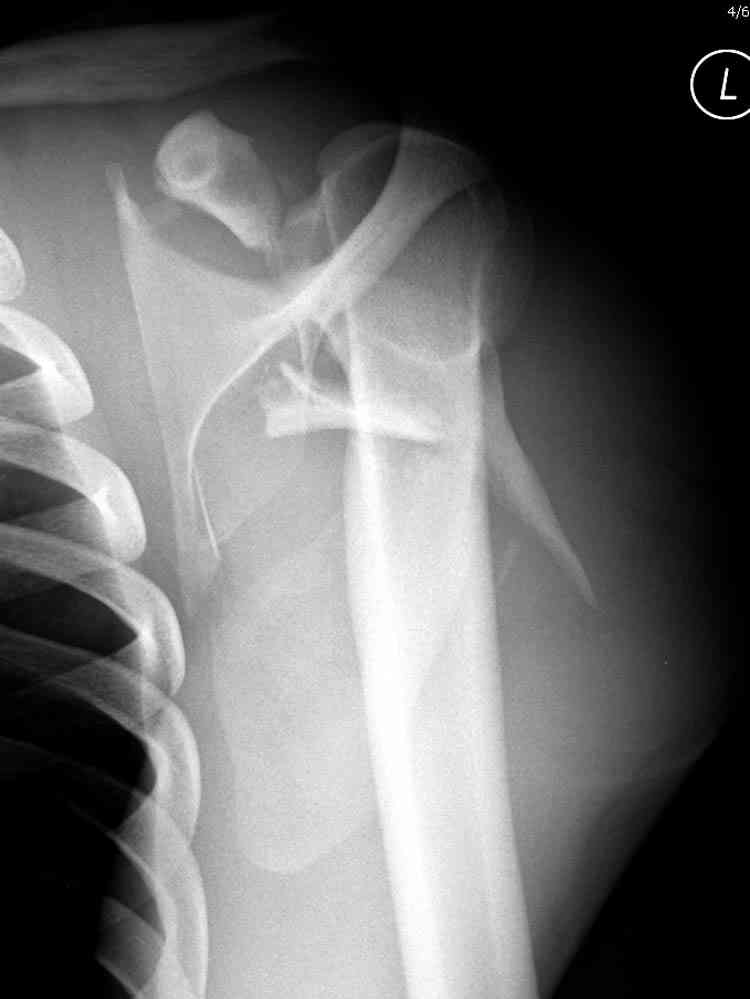

дравствуйте, коллеги. Мужчина 24 лет. Сегодня был прооперирован по Сушко-Илизарову (давно порывался, наконец-то руки дошли :)) На снимке перелом угла лопатки. Довольно крупный размер осколка. Следует ли оперировать такой перелом?Если есть резон оперативного лечения, то каким образом? (рекон. пластина, закрыто пришпилить спицами, винтами). ЭОПа в наличии нет. В области лопатки массивный отек мягких тканей. С уважением, Заднепровский Никита Николаевич

А где там сломанный угол лопатки? Стрелочкой покажите pls?

Посмотрел пациента под рентгеноскопом, определяется изолированный перелом верхнего медиального угла лопатки. Вопрос об операции отпал. Больной машет крылом как пропеллером, пришлось ограничить активность дисциплинирующей "косынкой" ... :))) Отек мягких тканей в области